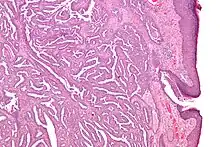

Micrograph of a nipple adenoma. H&E stain.

Once excised, the macroscopic appearance of nipple adenomas is of a poorly defined nodular mass. The microscopic appearance can be quite bizarre, and may be misinterpreted as a carcinoma. Nipple adenomas usually have a rounded outline at low magnification, and at higher magnification can be seen to consist of a haphazardly arranged mass of proliferating tubular structures composed of epithelial and myoepithelial cells within varying amounts of fibrous stroma. The epithelial cells are usually columnar, but the columnar epithelial cells can undergo apocrine or squamous metaplasia. Mitotic figures and necrosis are not commonly seen.[1]